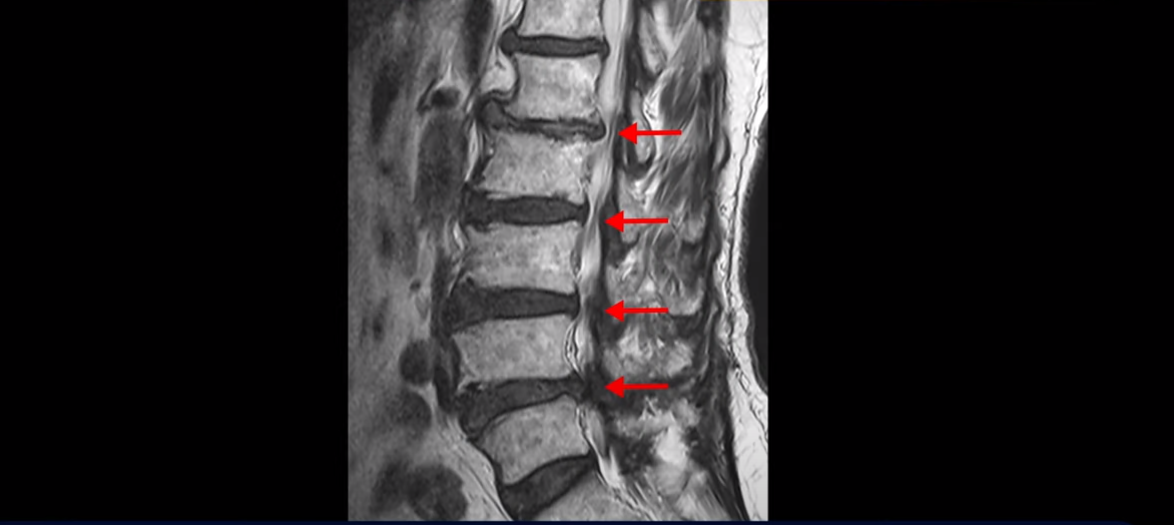

이분 MRI를 보면 척추의 여러 마디가 퇴행이 진행되어 안 좋습니다.

특히 4번 5번 마디가 제일 안 좋은데 보시다시피, 하얗게 보여야 될 신경이 거의 안 보일 정도로 척추관이 좁아져 있습니다.

이분은 허리도 아프지만 왼쪽 엉덩이와 다리가 너무 심하게 저리고 아팠는데 역시나 왼쪽 신경 가지가 빠져나가는 구멍이 막혀 있어서 매우 어둡게 보입니다.